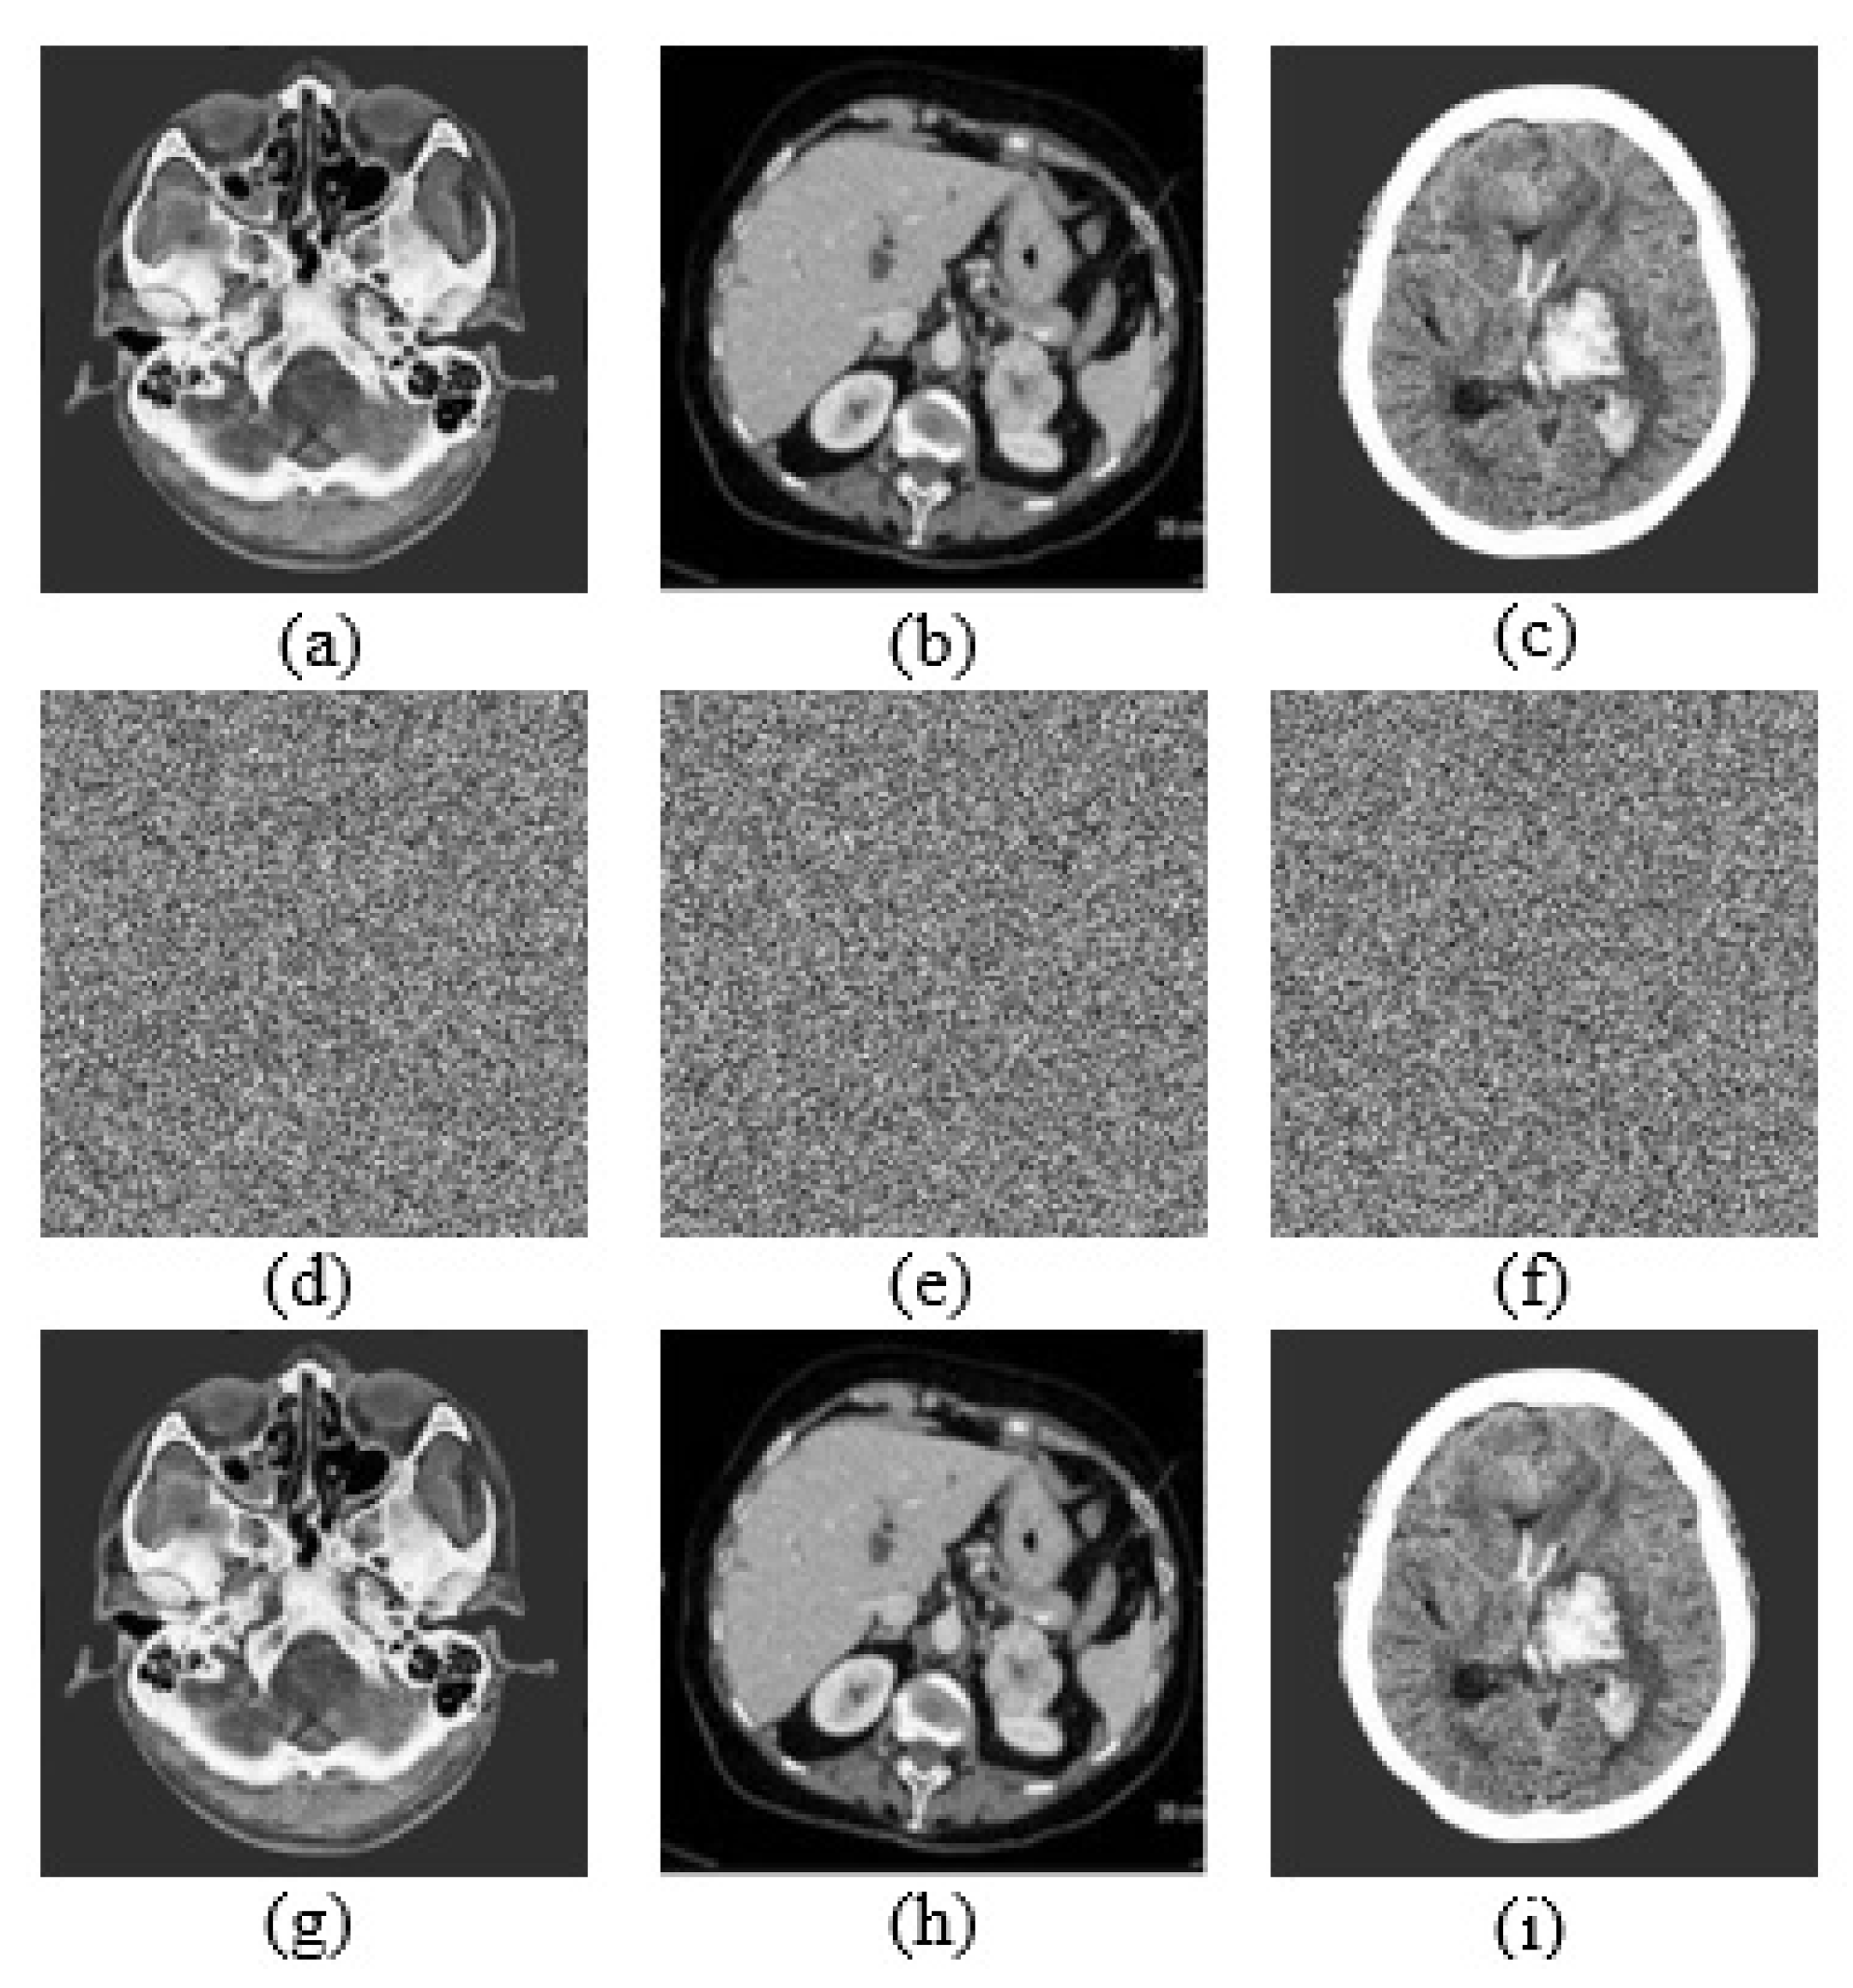

The implementation results of the encryption algorithm based on oscillator with butterfly attractors is shown in Figure 25.

The results in Figure 25 clearly show that when the algorithm is applied to the original images, the resulting encrypted images are totally different from the original ones. It also shows that after the reverse process, the images obtained are practically identical to the original ones.

Figure 25. Implementation results of the encryption algorithm based on oscillator with butterfly attractors. (a) Plain image of Cerebral Infarction, (b) plain image of Kidney Cancer, (c) plain image of Intracerebral Hemorrhage, (d) encrypted image of Cerebral Infarction, (e) encrypted image of Kidney Cancer, (f) encrypted image of Intracerebral Hemorrhage, (g) decrypted image of Cerebral Infarction, (h) decrypted image of Kidney Cancer, (i) decrypted image of Intracerebral Hemorrhage.